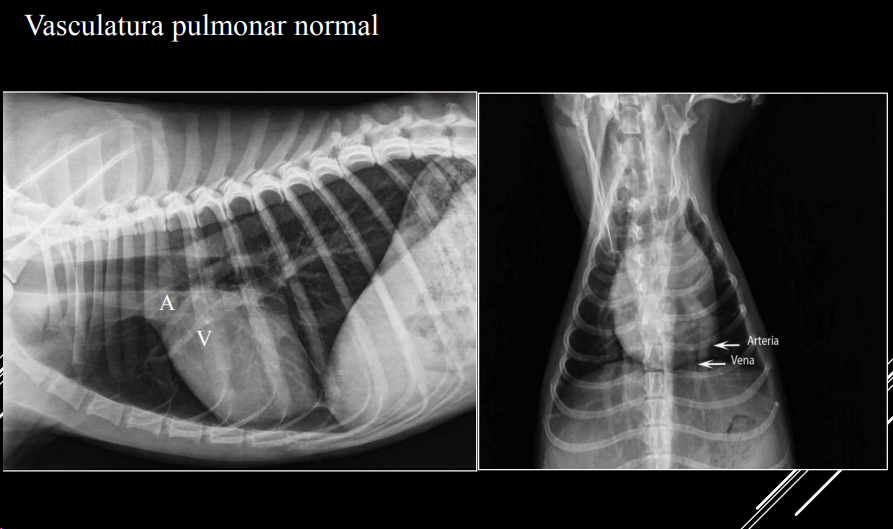

PATRÓN VASCULAR

- Cambios en tamaño, densidad o forma de vasos.

- Arteria y vena lobulares craneales del mismo tamaño.

- Comparación: grosor ≈ 4ª costilla (LL) o 9ª costilla (VD).

- Hipervascular o hipovascular.

- Posible mineralización (uremia, filariosis).

- Tortuosidad o cortes bruscos en arterias pulmonares → filariosis.